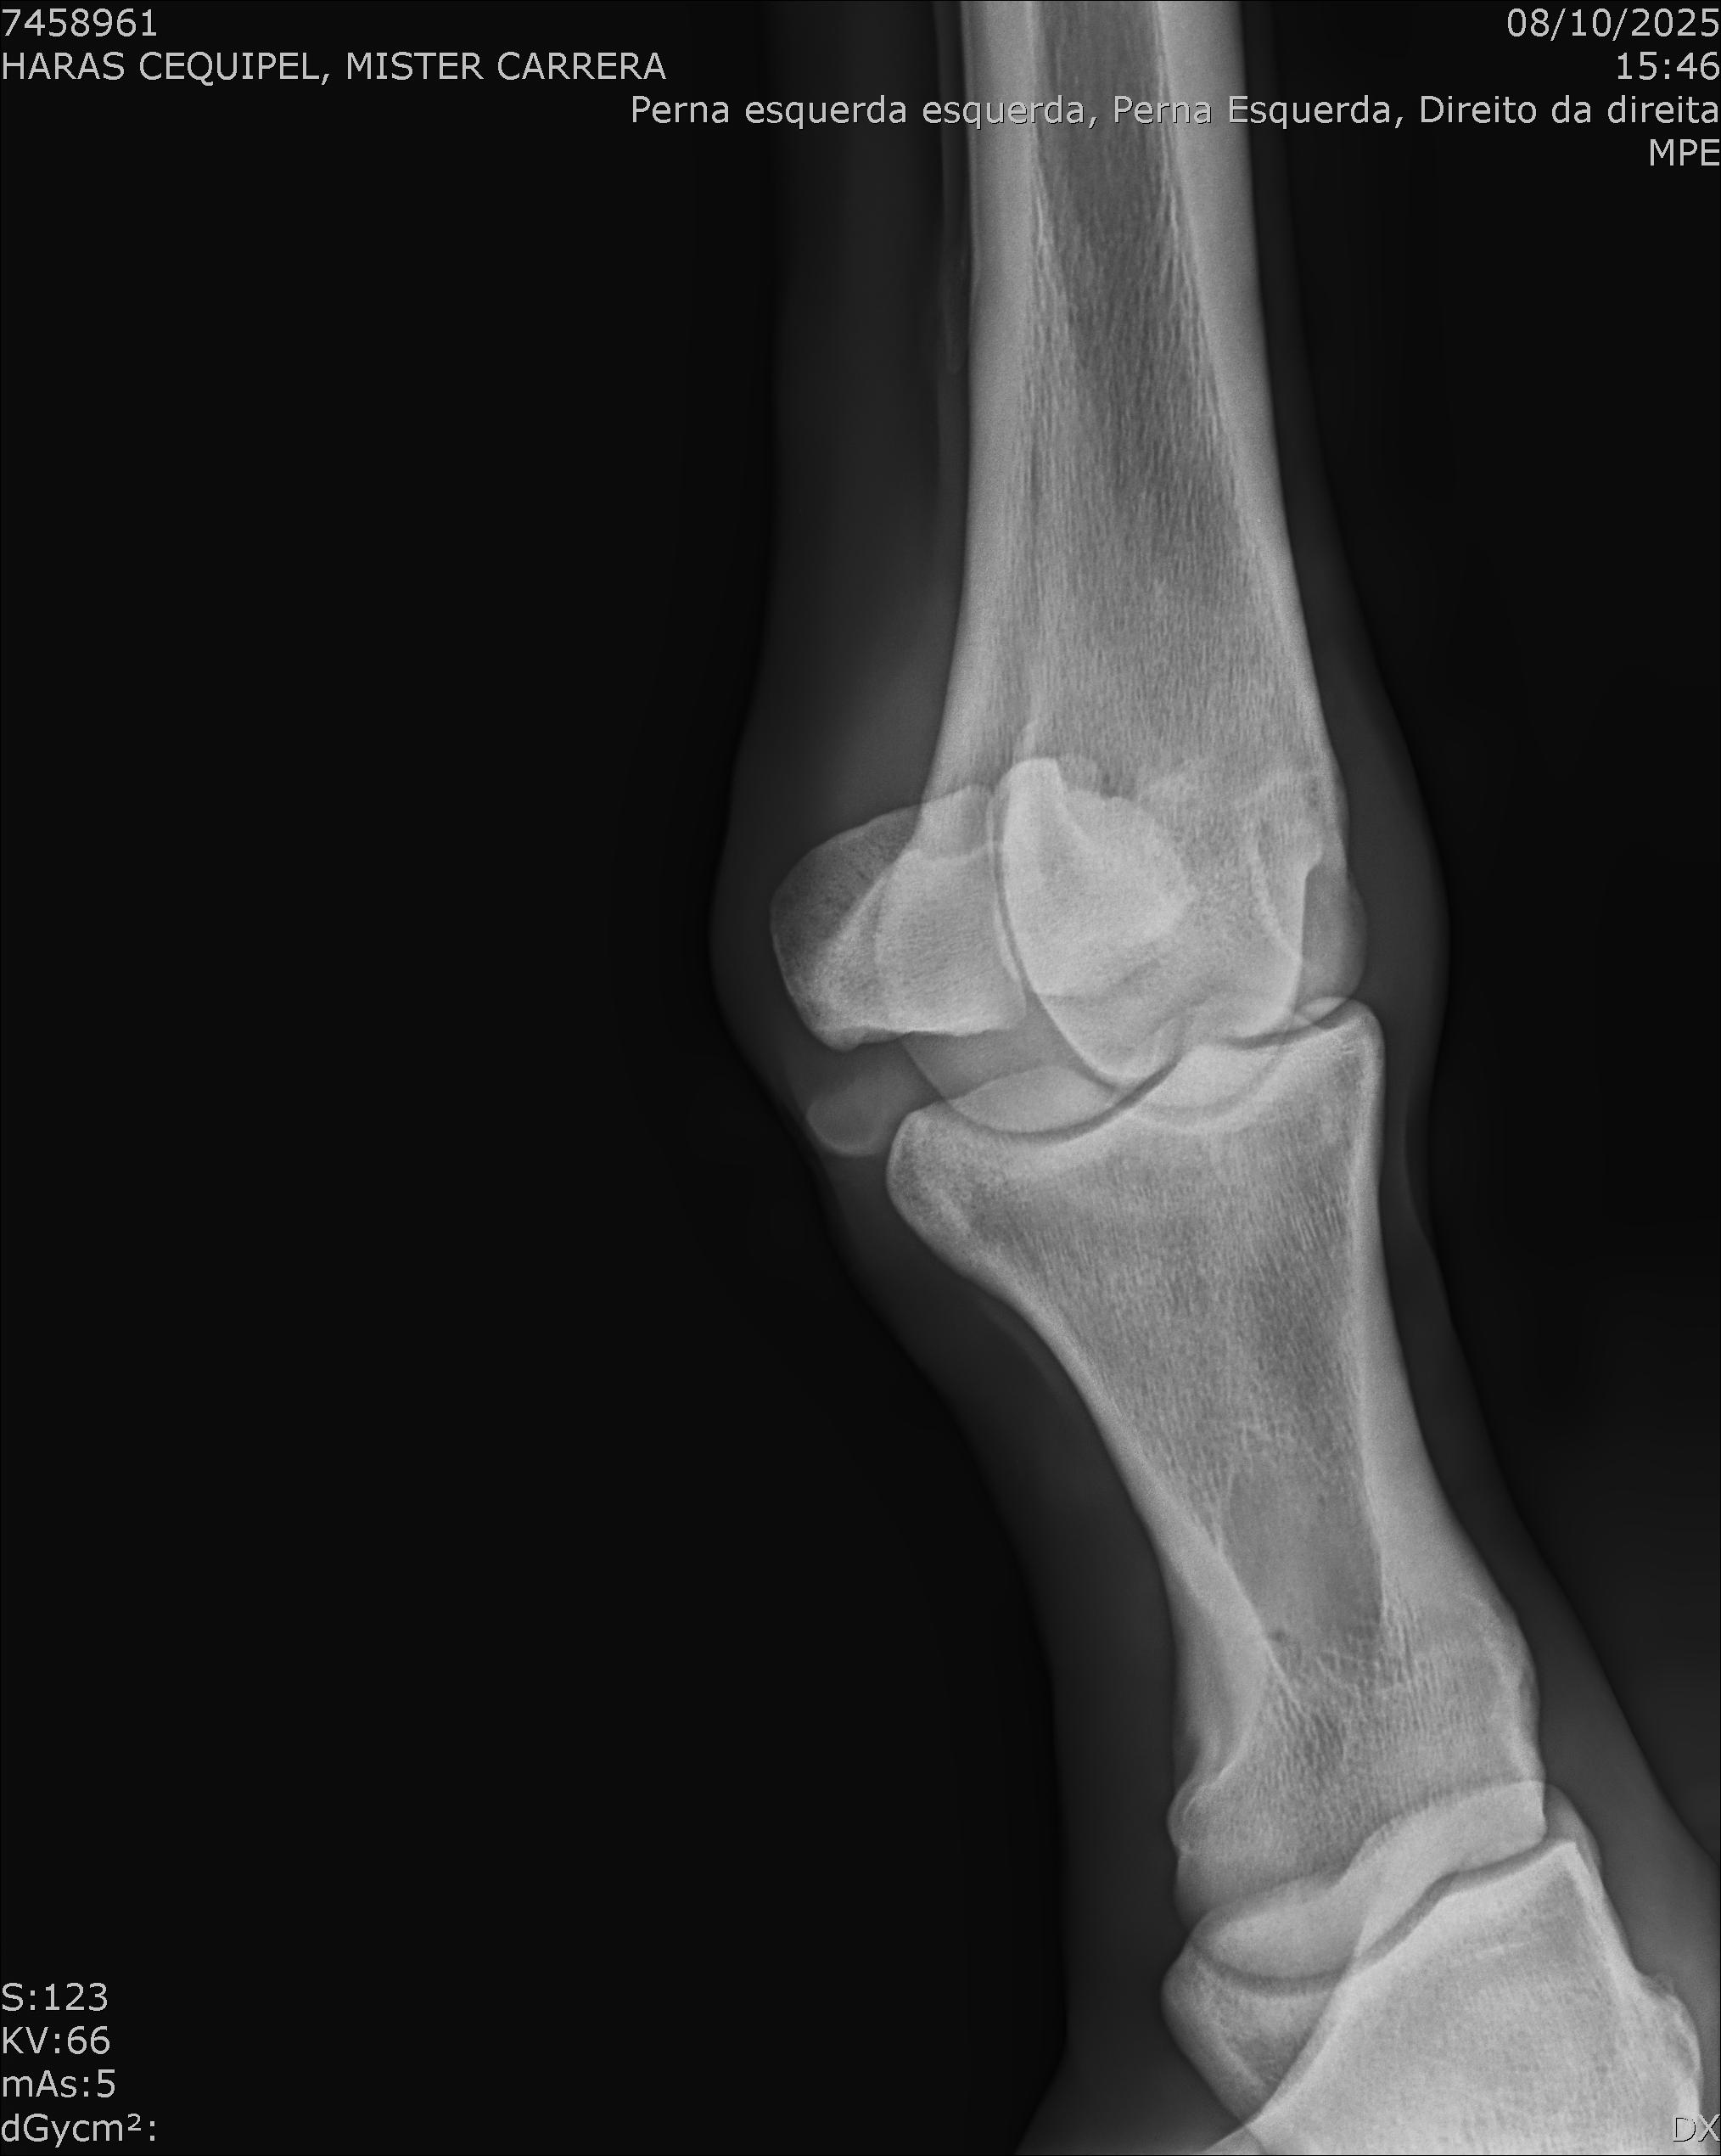

:: RAIOS-X DO LOTE